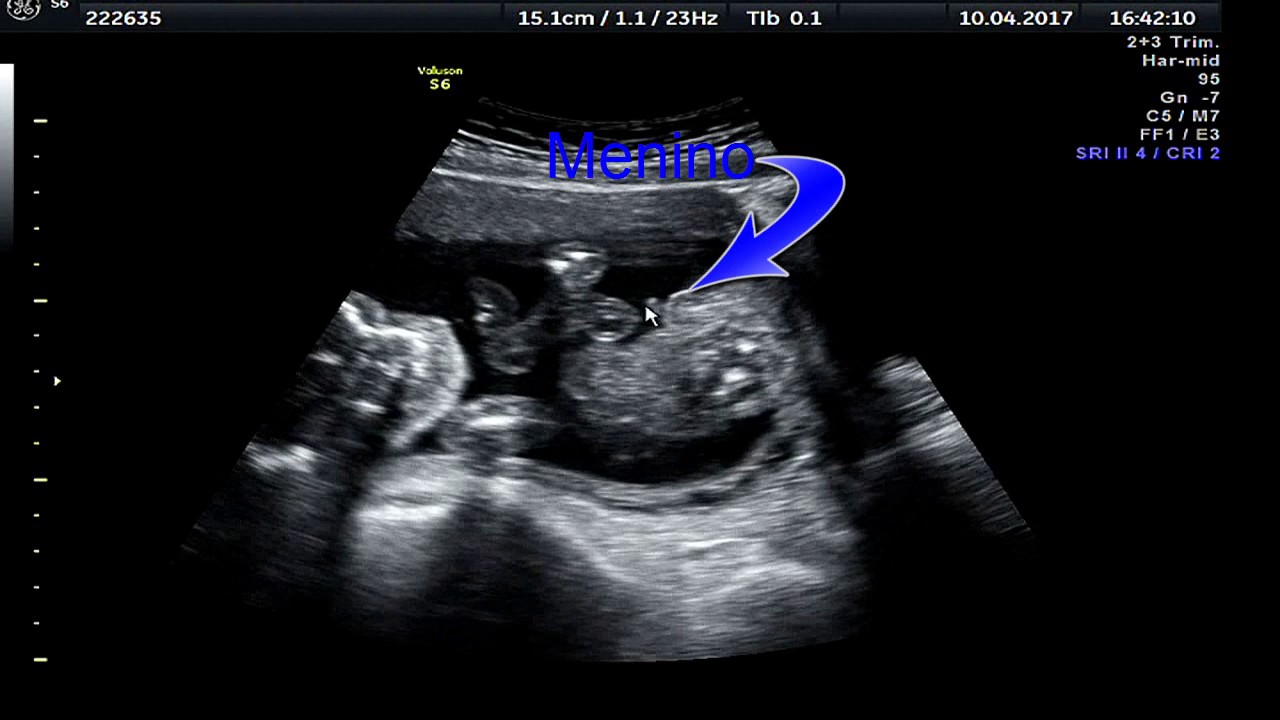

semanas 20 sexo bebê do ultrason

Webvocê já ouviu dizer que o bebê está cefálico, pélvico, córmico ou transverso? Esses termos se referem ao posicionamento do bebê dentro do útero. Os cabelos do couro cabeludo começam a se formar. Webo ultrassom na 20ª semana. O objetivo deste ultrassom é avaliar o desenvolvimento e o crescimento do feto, verificando a posição da placenta e dos órgãos e descartando.